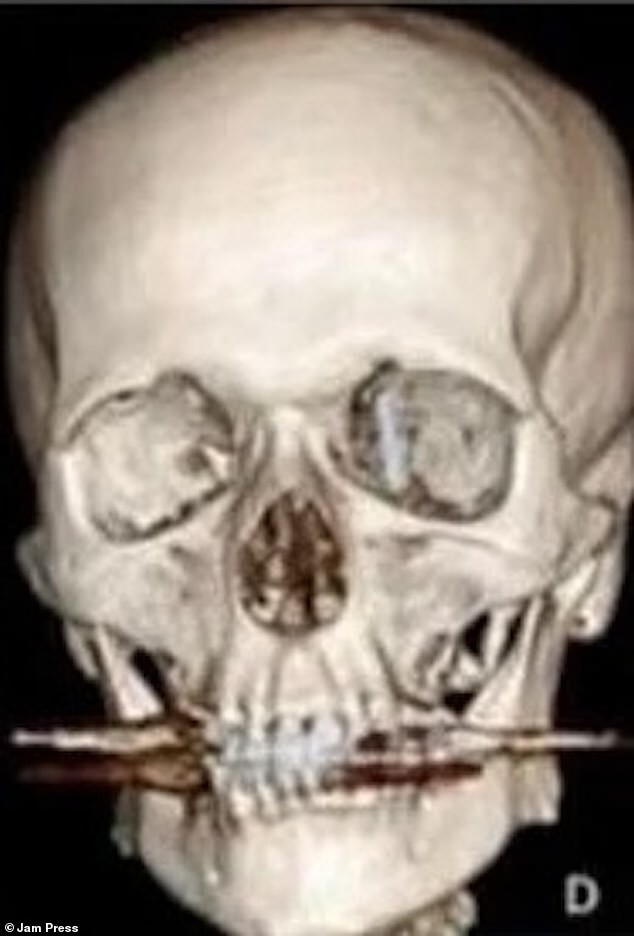

Но во время операции стоматолог, пытаясь вставить один из имплантатов на место, проткнул челюстную кость пациента.

Но когда он продолжил давить на винт, тот пробил мою челюстную кость и вошел в область за глазом, где находятся мозг и спинномозговая жидкость».

После обследования на томографе выяснилось, что винт вонзился в область, где находится мозг и спинномозговая жидкость. После этого врачи-эксперты собрались и приняли решение о проведении операции».